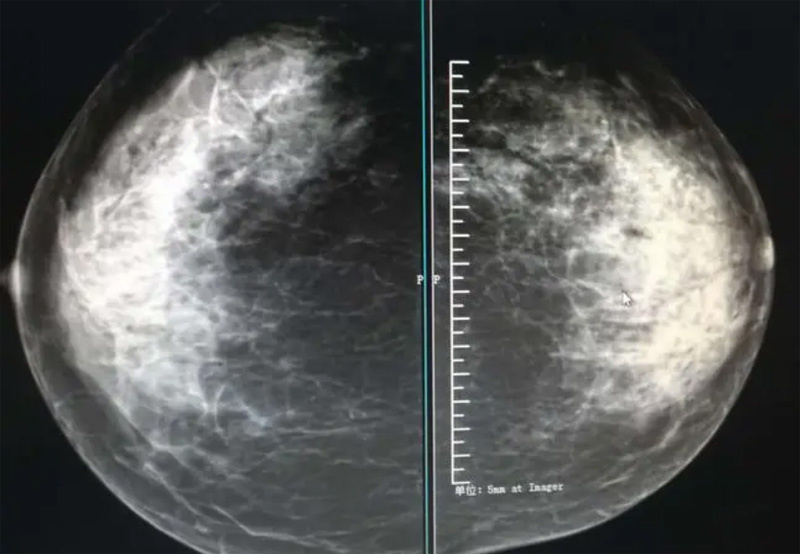

乳腺DR攝影體位有頭尾位及內(nèi)外側(cè)斜位,

乳房在片子的中央,乳頭切線位,可見小部分胸大肌,內(nèi)側(cè)乳腺組織應(yīng)全部包括在片中,外側(cè)乳腺組織盡可能包括在片中。一張好的MLO位圖像顯示如下:乳房被推向前上,乳腺實質(zhì)充分展開,胸大肌可見,較松弛,下緣達到乳頭水平,乳頭在切線位,部分腹壁包括在片中,但與下部乳腺分開,絕大部分乳腺實質(zhì)顯示在片中。乳腺組織外緣可見乳頭的輪廓;乳腺后方的脂肪組織被很好地顯示出來,乳房無皺褶。對于CC位及MLO位顯示不良或未包全的乳腺實質(zhì),可以根據(jù)病灶位置的不同選擇以下體位:外內(nèi)側(cè)位(LM)、內(nèi)外側(cè)位(ML)、內(nèi)側(cè)頭尾軸位(MCC)、外側(cè)頭尾軸位(LCC),尾葉位(CLEO)及乳溝位。在臨床實踐中,對于常規(guī)體位上發(fā)現(xiàn)的異常改變,可以進一步采取一些特殊的攝影技術(shù),包括局部加壓攝影、放大攝影或局部加壓放大攝影技術(shù)。